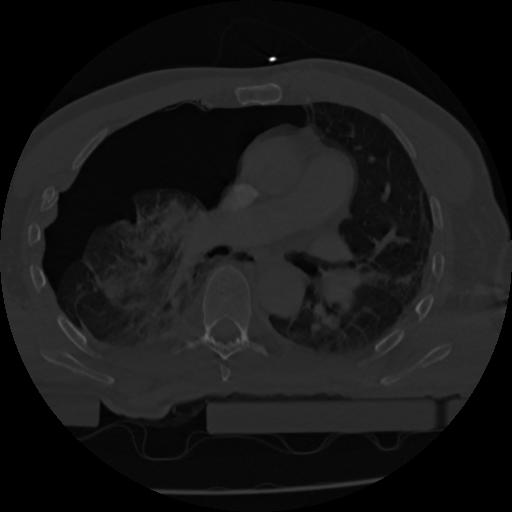

22 ANGIO,CE,Vol,0.5,ANGIO,,